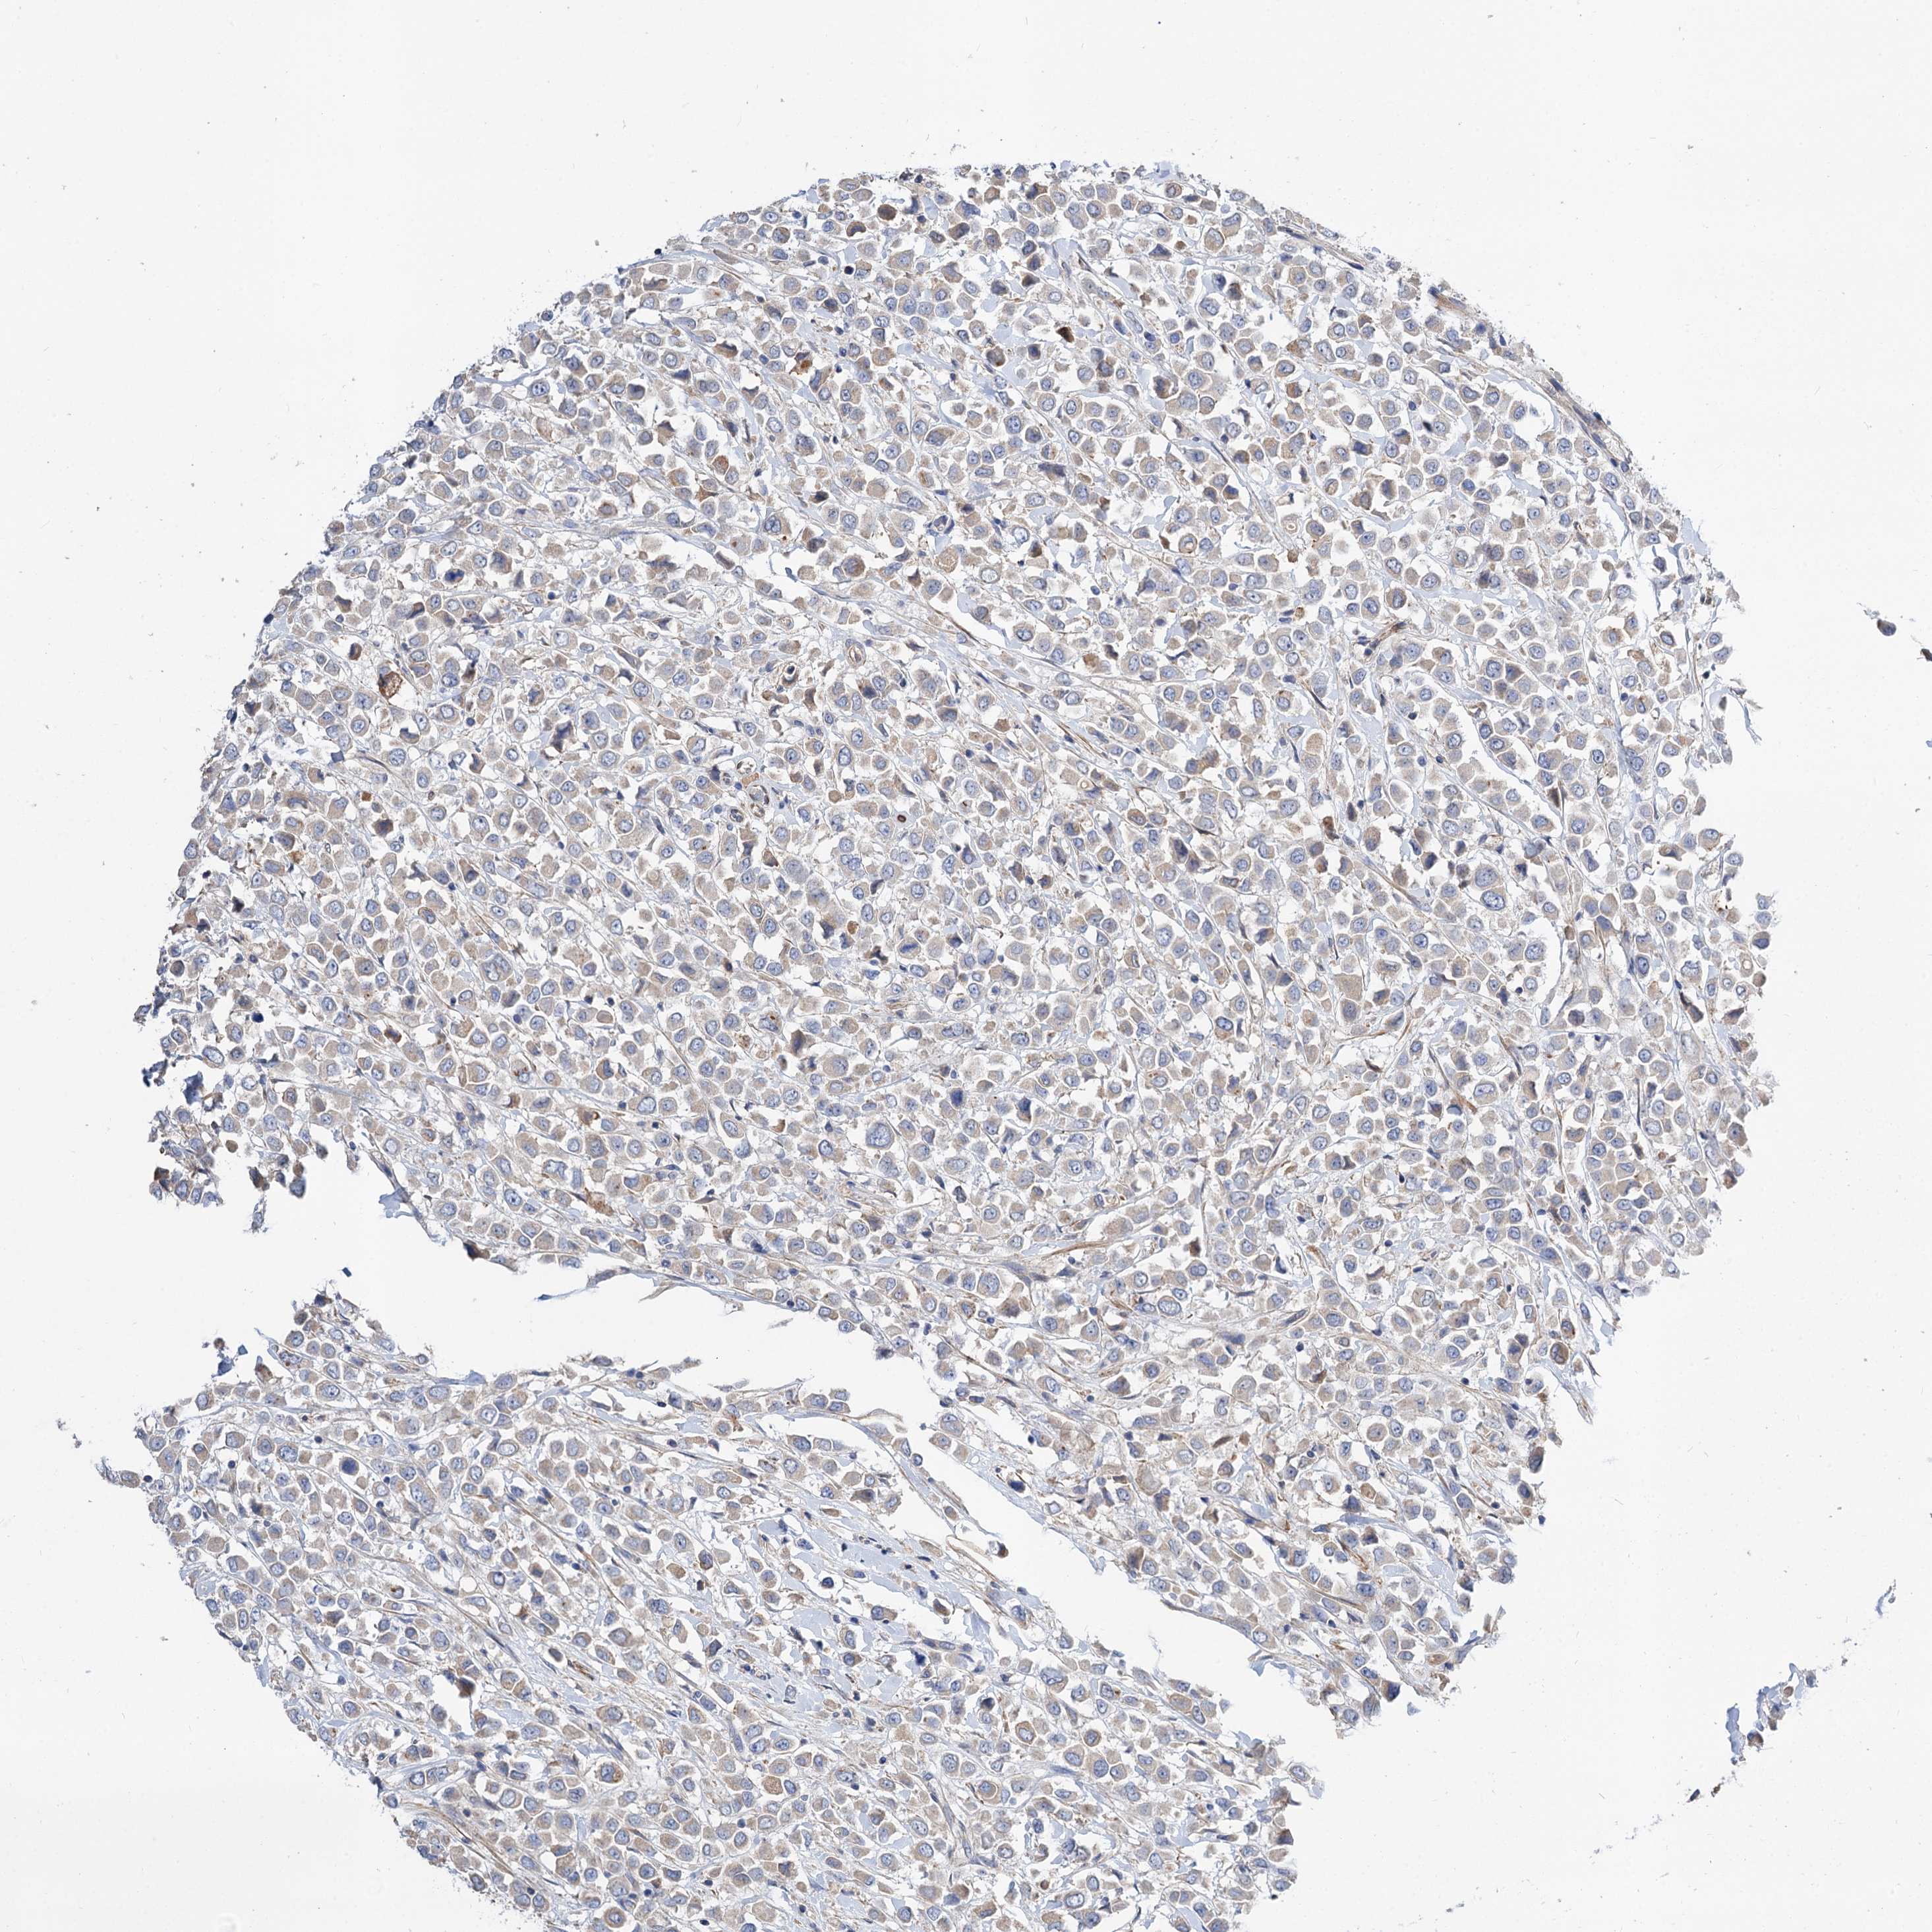

CANCER BREAST CANCER Show tissue menu

BRCA TCGA BRCA VALIDATION PROTEIN EXPRESSION